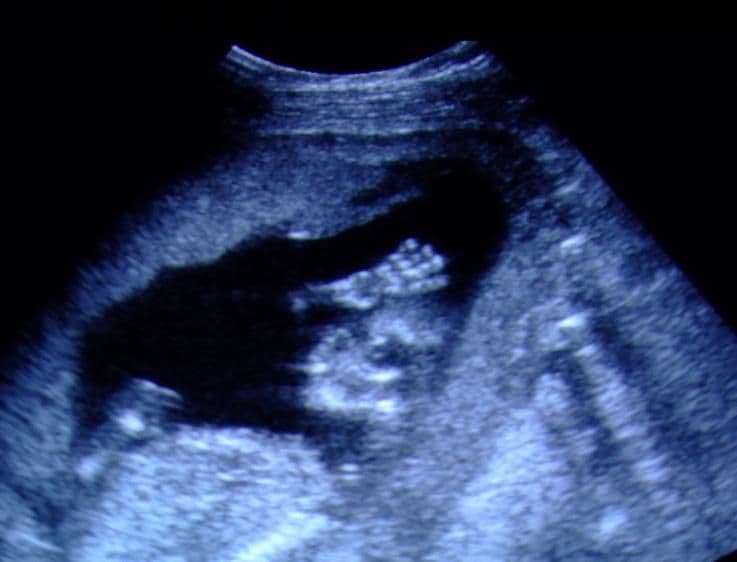

In this 2D ultrasound, the top of the baby’s head is in shadow, although the hand can be seen in front of the face. All the bones are growing and maturing at this stage of pregnancy.

At the same time your baby starts to develop hair follicles. There is no significant subcutaneous fat present at this stage and the skin is almost transparent. Fat plays a part in temperature control and acts as a barrier to the passage of water. These barriers are not yet in place so the skin is still very permeable.